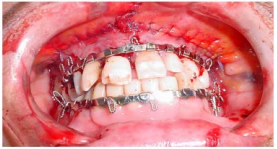

A imagem abaixo ilustra a técnica de bloqueio maxilomandibular com barras de Erich, que é utilizada no

tratamento de fraturas da face com o objetivo de:

Provas

Questão presente nas seguintes provas